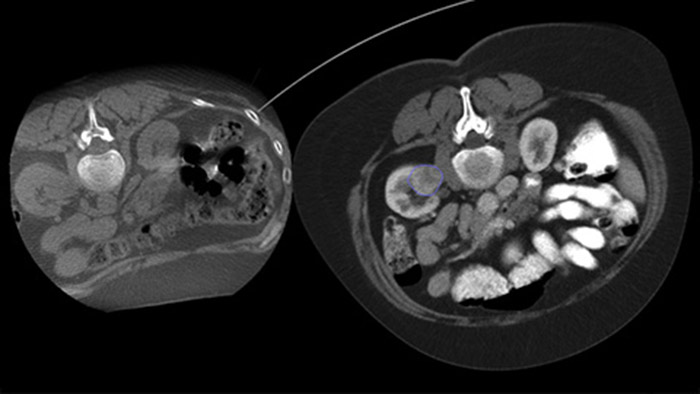

L’ablation percutanée (radiofréquence, micro-ondes et cryoablation) est un traitement peu invasif bien établi des tumeurs des reins, du foie, des poumons et des os. Il est essentiel de définir les limites de la tumeur et de décider d’un nombre optimal d’aiguilles et de la trajectoire d’aiguille correspondante afin de pouvoir effectuer un traitement complet de la tumeur sans endommager les tissus environnants. Une navigation précise à faible dose vers la lésion concernée sans repositionnement de l’aiguille augmente les chances de réussite et réduit le risque de complications de vos biopsies ou de vos ablations. La confirmation du point final du traitement d’ablation s’effectue avec l’imagerie 3D lorsque le patient est encore sur la table.

Grâce à CBCT, faites l’acquisition d’une image CBCT après ablation pour démontrer l’étendue de la couverture tumorale et confirmer l’exhaustivité du traitement.